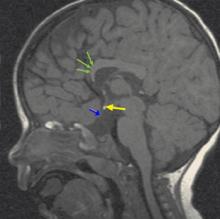

Magnetic resonance imaging (MRI) of the brain (FIGURE 2) revealed hypoplastic genu of the corpus callosum, cavum septum pellucidum, ectopic posterior pituitary, and small anterior pituitary. There was also enhancement of the inferior hypothalamus.

FIGURE 2

MRI of the brain

In addition to a full history and physical with dilated fundus exam, one of the most valuable tools in the diagnosis and prognosis of a patient with septo-optic dysplasia is an MRI of the brain with and without contrast, including the pituitary gland. In addition to detecting severely hypoplastic optic nerves, an MRI may also reveal the condition of the septum pellucidum and corpus callosum, cerebral hemispheric abnormalities, and pituitary ectopia. The presence or absence of these findings can help predict the clinical course in relation to pituitary function and neurodevelopmental delay.9,11